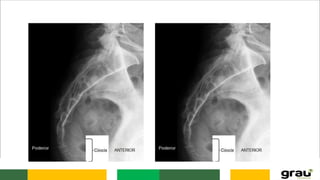

CURVATURAS: Primárias e secundarias

IMPORTÂNCIA CLINICA: hipercifose, hiperlordose escoliose

COLUNA VERTEBRAL CURVATURAS: Primáriase secundarias IMPORTÂNCIA CLINICA: hipercifose, hiperlordose escoliose Caracteristicas das vértebras permitem identificar a que região pertencem.